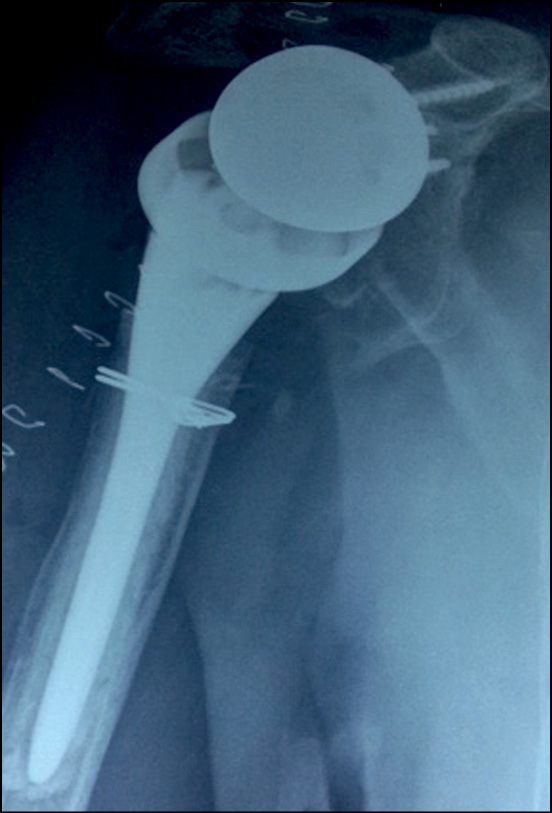

При клиническом и рентгенологическом обследовании пациентов выявлено 2 случая (8,7 %) перипротезного перелома, 1 из которых произошел интраоперационно. У 3 пациентов (13,2 %) выявлен вывих эндопротеза: зафиксировано 2 случая вывиха плечевого компонента, вследствие ранних сроков нагрузок и объемов движений прооперированной конечности (рис. 1), а 1 пациент пострадал от разобщения гленосферы с метагленом, и в последствие ее вывихом (рис. 2).

Рис. 2. Рентгенограмма пациента с вывихом гленосферы

Fig. 2. X-ray of a patient with dislocated glenosphere

Одному пациенту с вывихом плечевого компонента под общей анестезией успешно выполнено закрытое устранение вывиха, которое не потребовало дальнейшей открытой операции.

Двоим из трех пациентов с вывихом эндопротеза проведена ревизионная операция по устранению разобщения компонентов, в том числе установка гленосферы в положенную, стабильную позицию (рис. 3).